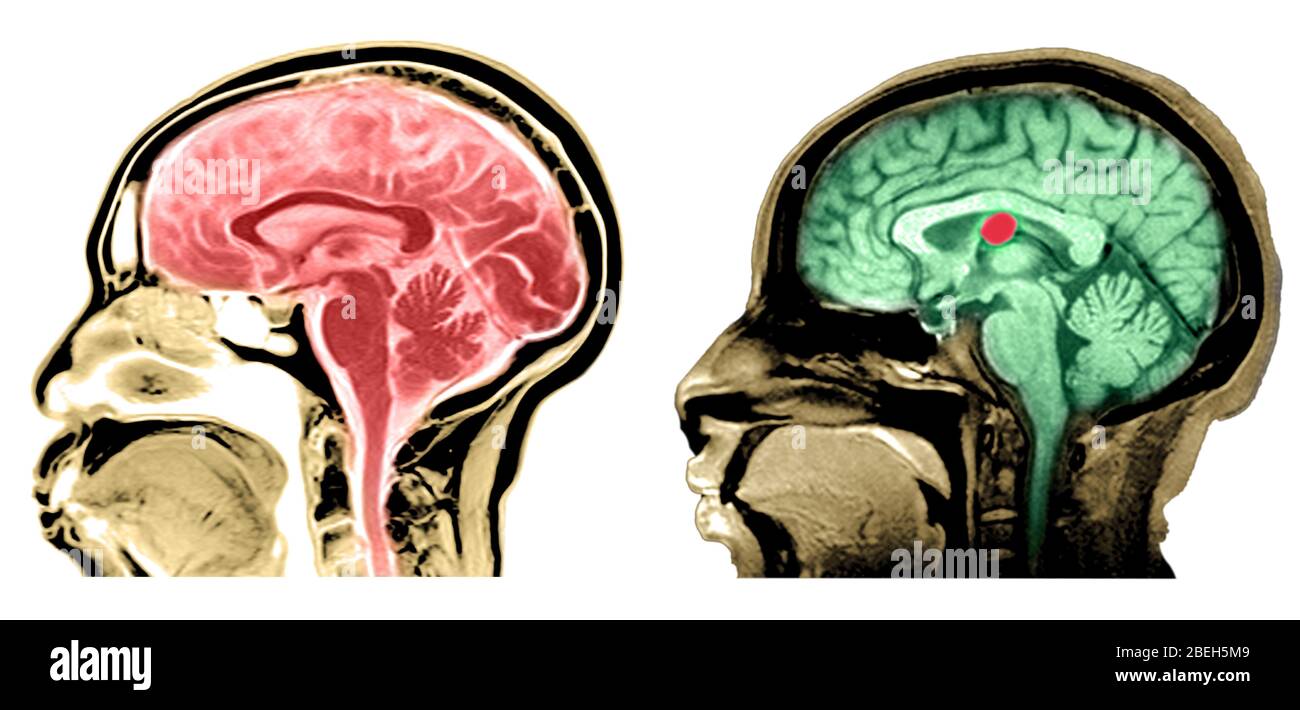

RF3CN8WHW–Darstellung der vergrößerten lateralen und dritten Ventrikel des Gehirns (Hydrozephalus), hervorgerufen durch einen Hirntumor, der den Aquädukt des Gehirns komprimiert.

RF3CN8WHP–Illustration des vergrößerten lateralen und dritten Ventrikels des Gehirns (Hydrozephalus), hervorgerufen durch einen Hirntumor, der den Aquädukt des Gehirns komprimiert.

RF3CPM9D2–Darstellung der vergrößerten lateralen und dritten Ventrikel des Gehirns (Hydrozephalus), hervorgerufen durch einen Hirntumor, der den Aquädukt des Gehirns komprimiert.

RF3CPM9D7–Darstellung der vergrößerten lateralen und dritten Ventrikel des Gehirns (Hydrozephalus), hervorgerufen durch einen Hirntumor, der den Aquädukt des Gehirns komprimiert.

RF3CPM9DA–Darstellung der vergrößerten lateralen und dritten Ventrikel des Gehirns (Hydrozephalus), hervorgerufen durch einen Hirntumor, der den Aquädukt des Gehirns komprimiert.

RF3CPM9D6–Darstellung der vergrößerten lateralen und dritten Ventrikel des Gehirns (Hydrozephalus), hervorgerufen durch einen Hirntumor, der den Aquädukt des Gehirns komprimiert.